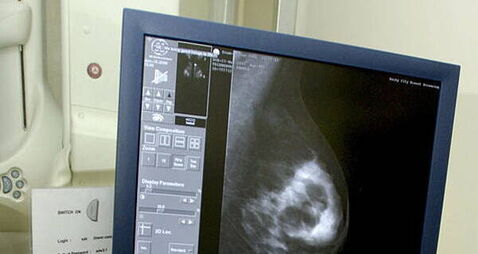

HSE says ‘problem’ with viewing BreastCheck register will be fixed next weekThe HSE said that the women are registered despite the system ‘not showing your correct details’.